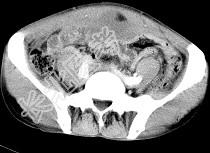

- 单项选择题男,56岁, 无规律上腹痛,左锁骨上淋巴结肿大, 消瘦、乏力,影像检查如图, 最可能的诊断是 ( )

C、胃癌并盆腔种植